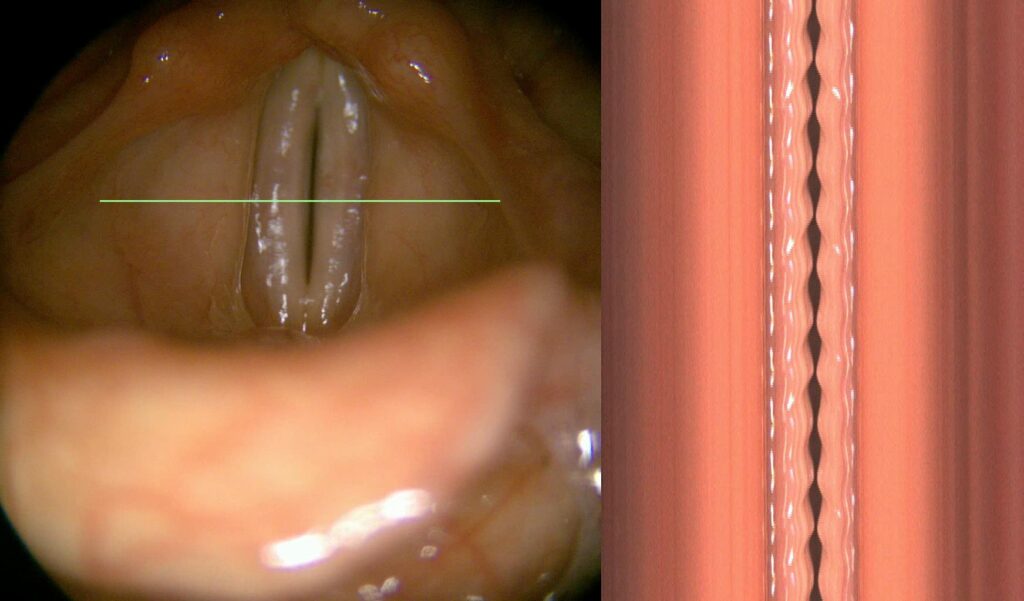

The visual information provided to the physician consists of two parts. The first part is an overview image used for navigation on the vocal cords and to indicate the specific location on the vocal cords from which the kymogram is obtained. The second part is the kymogram itself. A kymogram is therefore visual data from a high-speed camera, in our case 6500 frames per second, where an image corresponding to the area below the green line on the overview image is superimposed. So, essentially, 6500 times per second, we look at what is happening below the green line, and for greater clarity, we display all these image segments from the area below the green line one below the other.

On a kymogram, the doctor can observe whether both vocal cords are vibrating, whether the amplitude is the same, how large it is, how long the vocal cords remain open compared to the duration of closure, and whether the vocal cords close completely at all. They can observe the symmetry of the vibration, the phase shift of the vibration, how long a single vibration lasts, and how this duration changes. Advanced features suitable for observation include the sharpness of the peaks—both medial and lateral—as well as various aberrations.